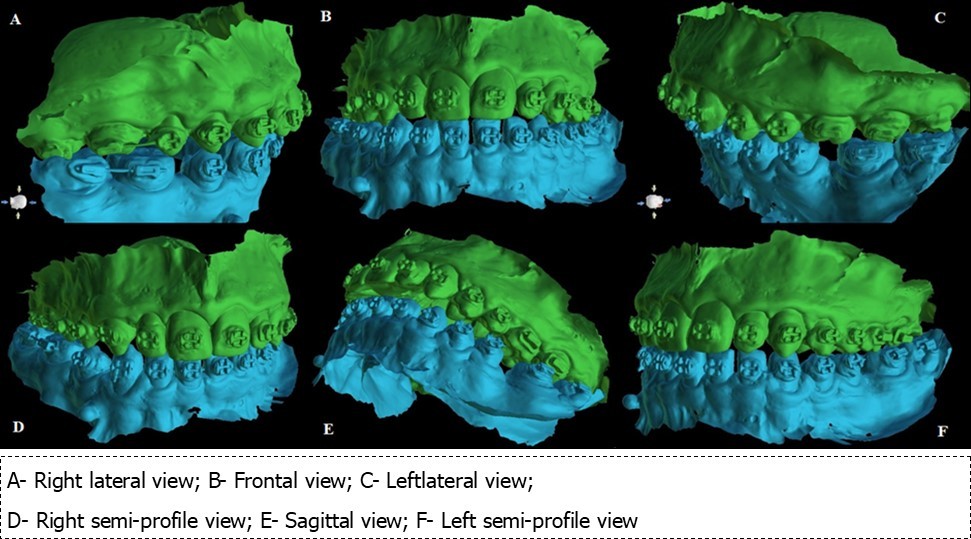

A CBCT scan was performed to determine the optimal site for mini-implants’ placement. Using the 3Shape Trios Intraoral Scanner the maxilla and the mandible were laser-scanned (Figure 1). Blue Sky Plan 4 software was used to design the surgical guide, and RayWare software was used for printing it.

The digital model (stereolitography (STL) files) was superimposed on the CBCT scan (DICOM file (Digital Imaging and Communication in Medicine) file in order to facilitate the optimal positioning of the 4 mini-implants in the anterior hard palate.